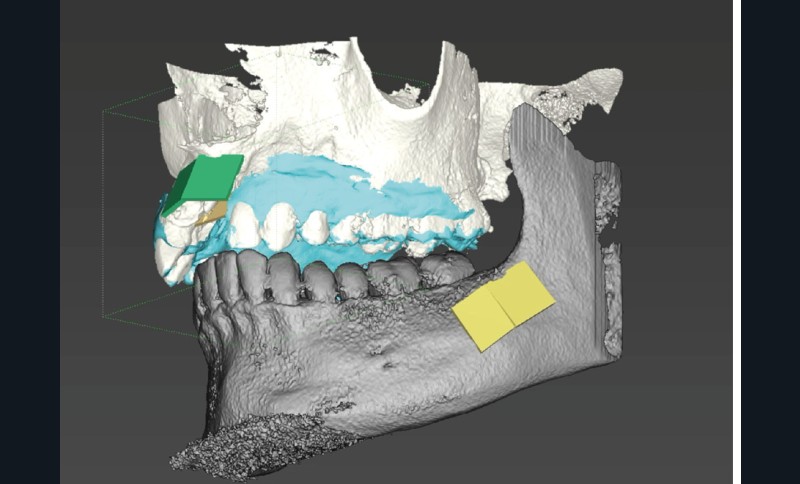

La chirurgie guidée dynamique permet, quant à elle, de prélever par piezochirurgie (Piezotouch, Mectron) de façon naviguée (fig. 3). Ainsi, le bloc peut être designé en amont sur le logiciel de planification implantaire pour correspondre parfaitement au défaut osseux en présence, et prélevé à l’identique sur la ligne oblique externe (fig. 4 à 8).